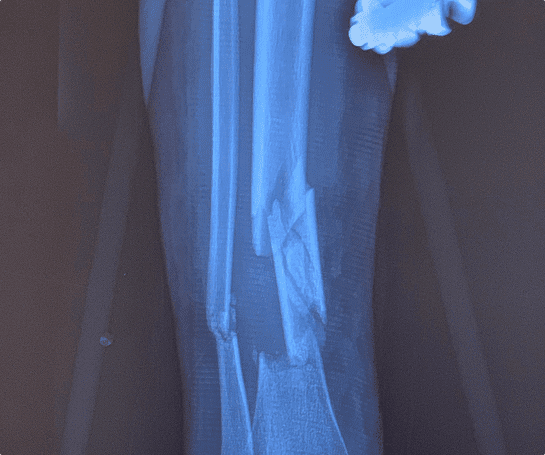

Open thigh/leg/foot/lower extremity fracture surgery is surgery most commonly used for treatment of fractures of the femur (thigh), tibia/fibula (leg), and foot.

Once in the operating room, you will be positioned so that a clear view of the fracture. A member of the surgical team will clean the skin over the fracture site with an antiseptic solution and a sterile drape will cover your lower extremity. Typically the incision is made over the fracture or area of reconstruction. Most fractures are treated with placement of plates and screws on the bone after alignment is restored. Some hand fractures are fixed with small pins underneath or through the skin. Flexible rods may be used in children once alignment is restored. At the end of surgery the incision is closed with stitches and covered them with a large, soft bandage.